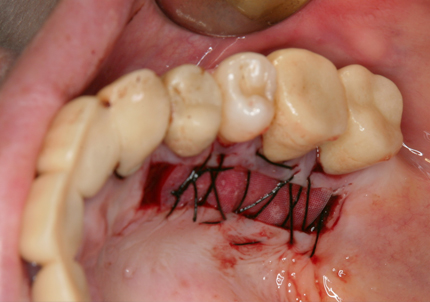

3.左下遊離歯肉移植術(F.G.G)(2009年6月)

再生療法後に付着歯肉消失の為、左下4・5・6・7番の付着歯肉の獲得を目的に遊離歯肉移植術(F.G.G)を選択する

口蓋より角化歯肉を採取して骨膜上に縫合する